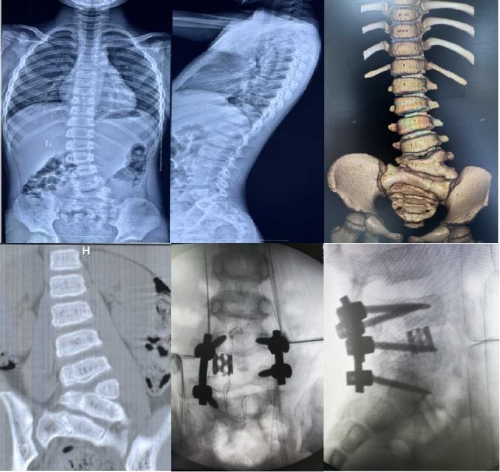

首先,邓幼文主任向仉建国教授介绍了科室的规模和布局以及文化建设。随后,邓幼文主任与仉教授沟通了关于人才培养和交流相关合作事宜。期间,仉建国教授对脊柱外科浓厚的文化氛围大加赞赏,同时表示北京协和医院骨科愿与湘雅三医院脊柱外科在人才培养和学术交流上加强合作。最后,邓幼文主任带领的新湘雅脊柱侧弯团队携手湘雅三医院客座教授、北京协和医院骨科主任仉建国为一位先天性脊柱侧弯患儿顺利完成半椎体切除+脊柱矫形手术。

仉建国教授在脊柱侧弯矫形方面具有深厚的造诣,目前已完成近5000例脊柱矫形手术,其治疗的患者构成了世界上最大的半椎体切除病例数据库,并且在全世界首次提出了截骨联合生长棒技术治疗重度早发性脊柱侧凸,同时参与创立了特发性脊柱侧凸协和分型(PUMC分型),2005年获得国家科技进步二等奖。此次携手新湘雅脊柱侧弯团队开展的脊柱侧弯矫形手术,为仉建国教授受聘中南大学湘雅三医院客座教授后在湘雅三医院开展的首例手术。